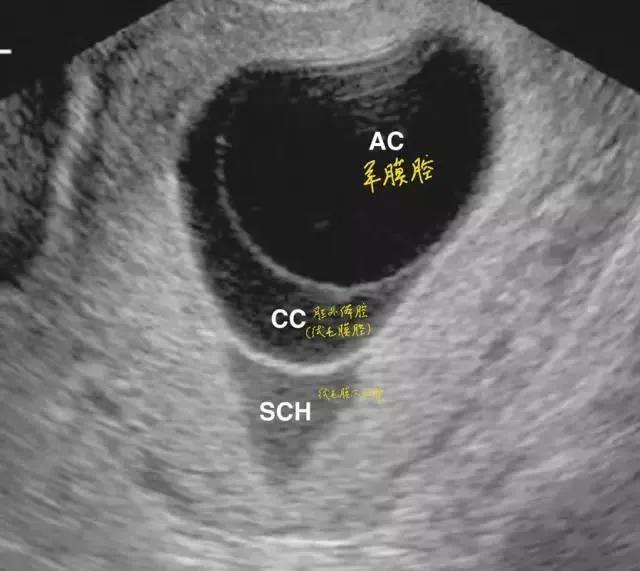

绒毛膜下血肿是指由于绒毛膜与蜕膜之间分离,局部出血积聚而成。不同大小的血肿总是在叶状绒毛膜、平滑绒毛膜与底蛻膜、包蛻膜之间。超声检查可见胎膜与蜕膜部分剥离,其间呈无回声液性暗区,血肿较大有凝血块时其内可见点状、线状或云状高辉度像,轮廓较明显,常位于胎盘下缘,多呈新月状,其血肿下缘常与子宫内口相通,而出现阴道流血。多发生早中孕期。报道的发生率为4%~48%不等。

- 绒毛膜下血肿的超声声像表现为液体集聚在妊娠囊与子宫壁之间,可呈新月形、圆形等多种形状,液体外形取决于子宫的形态变化。血肿局部多普勒检测不到血流信号。